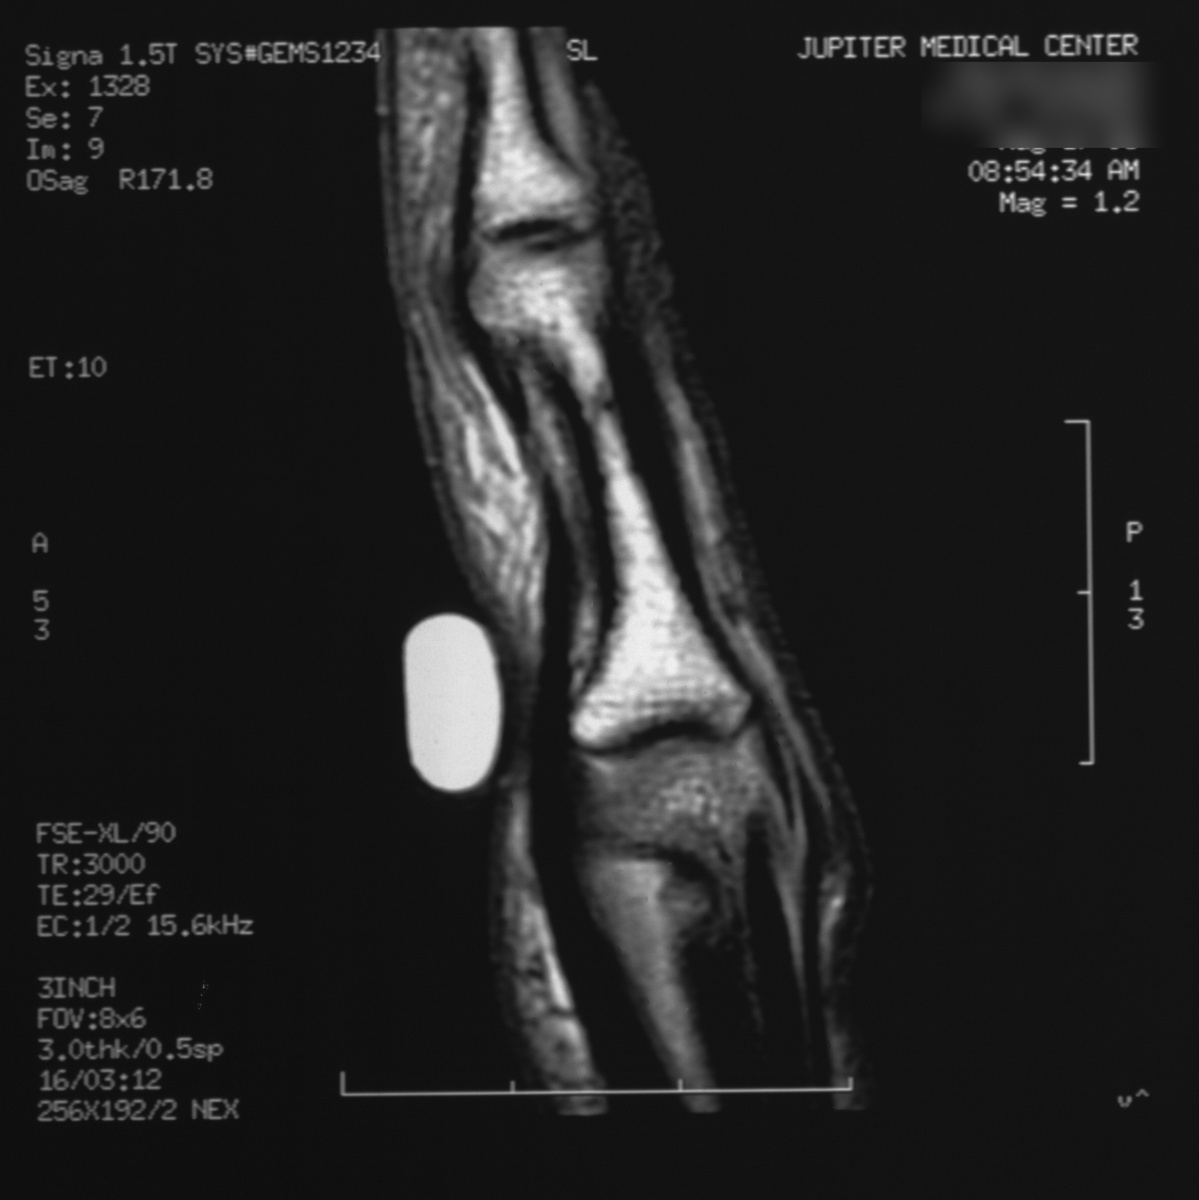

| MRI confirmed a cortical

nidus. |